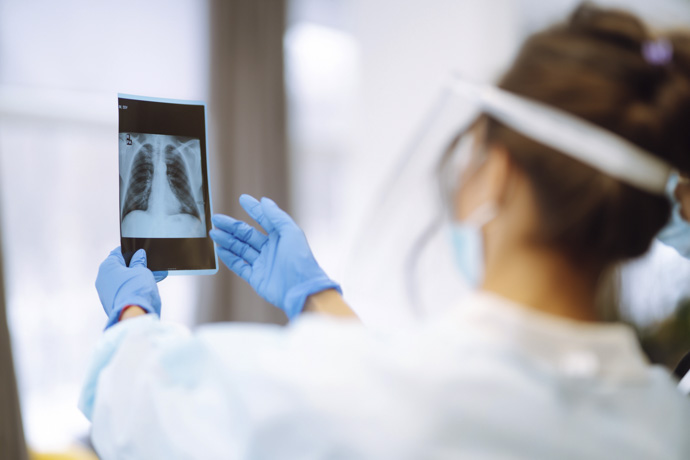

La detección de nódulos u opacidades pulmonares (comúnmente referidos como “manchas en los pulmones”) no es sinónimo de malignidad. Con frecuencia, estos hallazgos son de naturaleza benigna y pueden corresponder a lesiones cicatriciales residuales de infecciones previas, como la tuberculosis u otros procesos inflamatorios. Sin embargo, dado que en ciertos casos pueden constituir un signo temprano de cáncer u otras patologías activas, es crucial realizar una evaluación médica exhaustiva y una correcta interpretación de las pruebas de imagen para determinar con precisión su etiología.

Diagnóstico de manchas en los pulmones

La Universidad Clínica de Navarra resalta que las manchas en los pulmones se diagnostican, por lo general, de forma incidental. Aunque también hay programas de diagnóstico precoz que pueden ayudar a detectarlas y reducir significativamente el riesgo de complicaciones asociadas a ellas.

En una gran parte de los casos no hace falta realizar pruebas adicionales, ya que basta con realizar chequeos cada cierto tiempo para evaluar su estabilidad. En otros, es posible que el médico requiera analizar a profundidad los nódulos y solicite al paciente alguno de estos exámenes:

- TAC (escáner) de tórax de baja dosis de radiación: permite obtener imágenes muy detalladas del pulmón con un nivel reducido de radiación, ideal para controles periódicos y para detectar cambios pequeños en tamaño o forma.

- Tomografías computarizadas: ofrecen una visión más completa de las estructuras internas, permitiendo diferenciar con mayor precisión entre inflamación, tejido cicatricial o masas sólidas.

La tomografía computarizada suele ser la herramienta principal para evaluar este tipo de hallazgos y compararlos con estudios previos, mientras que otras pruebas se indican solo en situaciones concretas, según criterio médico.

El proceso diagnóstico no siempre implica múltiples estudios; muchas veces basta con observar cómo evoluciona la mancha con el tiempo. La estabilidad es una señal tranquilizadora, mientras que los cambios estructurales pueden motivar evaluaciones más profundas.

Los especialistas suelen combinar la información de las imágenes con los antecedentes del paciente, sus síntomas y factores de riesgo, porque el contexto es clave para interpretar un hallazgo pulmonar. Un nódulo puede tener un aspecto similar en dos personas distintas, pero su significado clínico puede ser completamente diferente según la historia de cada una.